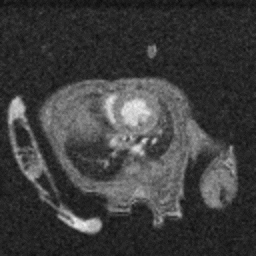

Anatomy & Morphology of mouse abdomen: T1- and T2- weighted scans of wildtype mouse body abdomen. Image Credit Scintica Instrumentation Inc

T1- and T2- weighted images of Wild-type mouse abdomen. Image Credit: Scintica Instrumentation Inc